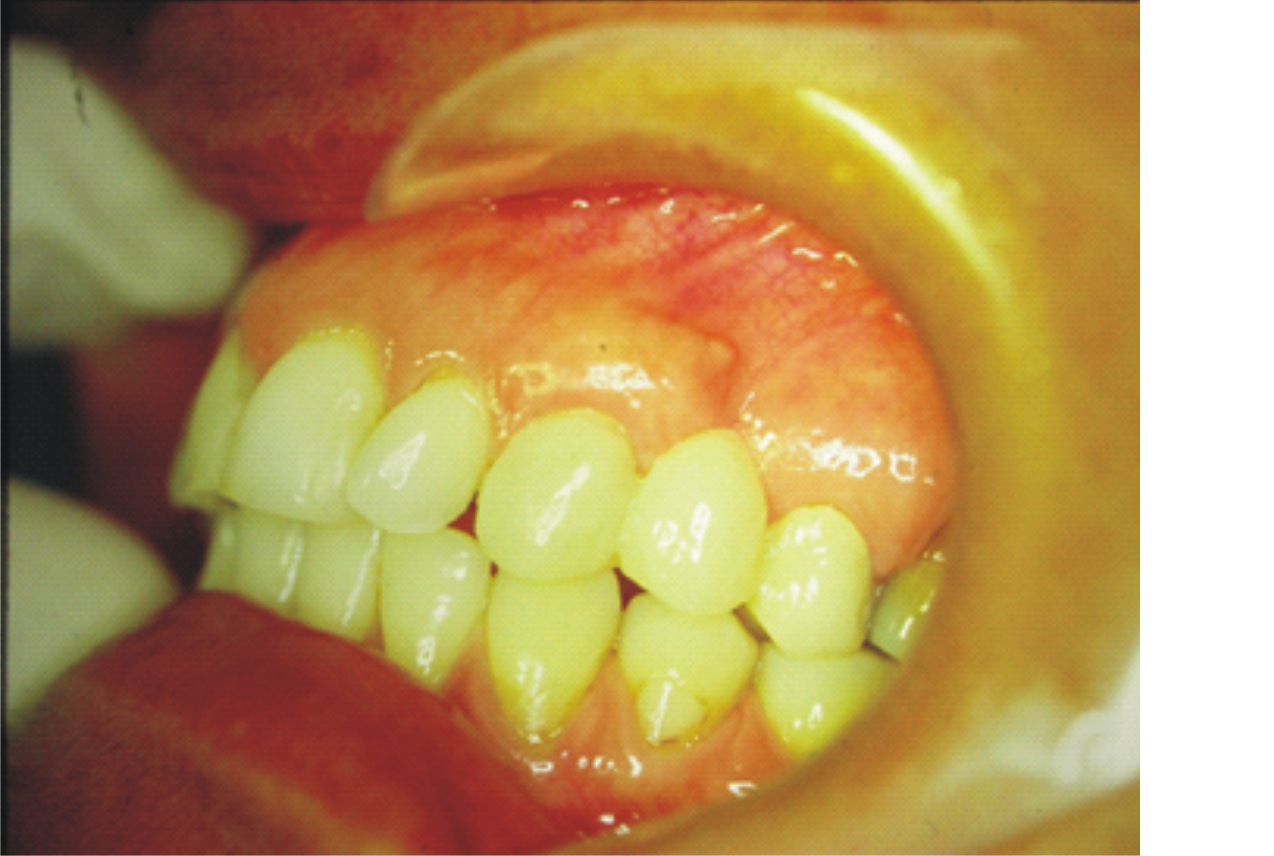

- Figura 1A (Português (Brasil))

- Figura 1B (Português (Brasil))

- Figura 1C (Português (Brasil))